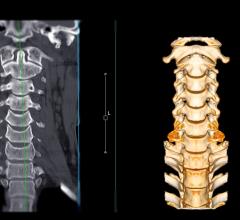

August 30, 2023 — A published study by researchers at the University of Cincinnati Cancer Center and Cincinnati Children ...